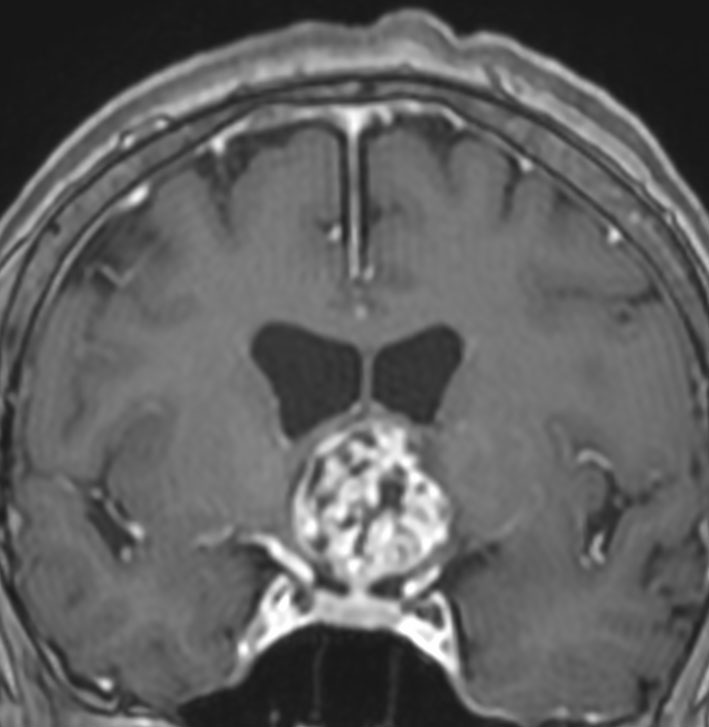

成人の第3脳室内部に局在する頭蓋咽頭腫です。経脳梁法で両側のモンロー孔から全摘出しました。下垂体組織は残っています。これは乳頭状頭蓋咽頭腫と呼ばれるもので,成人にしか発生しません,のう胞がなく石灰化もないのが大きな特徴です。境界が明瞭で柔らかく摘出が簡単なタイプとして知られています。この患者さんも術後に下垂体機能不全も視床下部障害も生じませんでした。